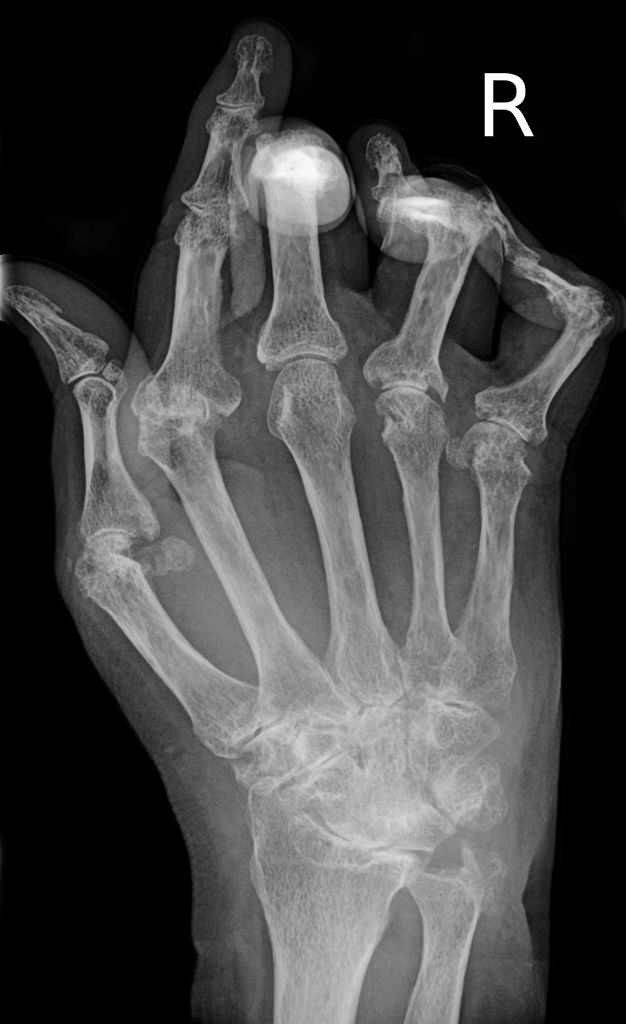

Entrenamiento de alta intensidad ayuda a aliviar dolores de artritis

La artritis es una enfermedad que se te escapa. Los dedos de los pies y los pies lentamente se vuelven rígidos y dolorosos. Un buen tramo de la mañana ya no es todo lo necesario para que su cuerpo se mueva. La artritis es una enfermedad crónica que hunde sus garras en su cuerpo y causa inflamación en sus articulaciones. Puede destruir sus articulaciones,